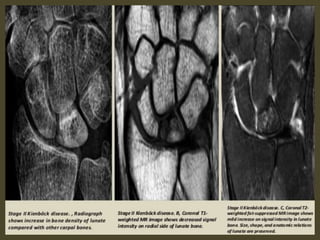

Keinbock,s Disease.